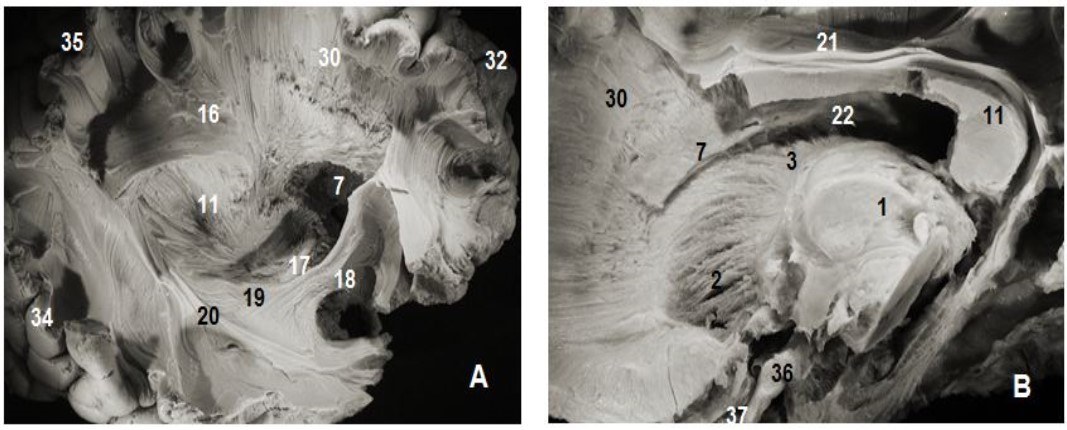

Figure 3.Thalamic radiations: (A) lateral view and (B) medial view. 1. Thalamus, 2. Anterior thalamic radiations, 3. Superior thalamic radiations, 4. Posterior thalamic radiations, 5. Inferior thalamic radiations, 6. Ventricular landmark, 10. Tapetum of corpus callosum, 11. Splenium of corpus callosum, 22. Ependymal membrane, 23 .Pons , 24. Mesencephalon, 17. Optic tract, 18. Uncinate fasciculus, 31. Occipital pole, 36. Cerebellum, 37.Frontal pole.

Thalamic radiations: (A) lateral view and (B) medial view. 1. Thalamus, 2. Anterior thalamic radiations, 3. Superior thalamic radiations, 4. Posterior thalamic radiations, 5. Inferior thalamic radiations, 6. Ventricular landmark, 10. Tapetum of corpus callosum, 11. Splenium of corpus callosum,  22. Ependymal membrane, 23 .Pons , 24. Mesencephalon, 17. Optic tract,  18. Uncinate fasciculus, 31. Occipital pole, 36. Cerebellum, 37.Frontal pole.

Thalamic radiations or thalamocortical pathways are reciprocal myelinated nerve fibers, arranged in a fanning pattern, grouped into tracts or fasciculi; and connecting the thalamus to the cerebral cortex (Figure 2, Figure 3, Figure 4). They are the most medial fibers of the internal capsule and consist of anterior (thalamofrontal), superior (thalamo-fronto-parietal or thalamoparietal), posterior (thalamooccipital) and inferior (thalamotemporal) thalamic fasciculi.

The thalamus sends fibers in all directions. Anteriorly, the thalamo-fronto-parietal fasciculus connects the anterior and medial lateral nuclei to the cortex of the frontal pole. Superiorly, the thalamo-parietal bundle unites the anterior and intermediate latero-ventral nuclei to the posterior frontal and prefrontal cortex, and the lateral postero-ventral nuclei to the sensory associative parietal cortex. Posteriorly, the thalamo-occipital fasciculus connects the lateral geniculate body and the posterior nucleus to the occipital cortex. Posterior and superiorly, the thalamo-parietal fasciculus connects the dorso-lateral nuclei to the posterior associative cortex.

Posterior and inferiorly, the thalamotemporal fasciculus unites the posterior nucleus and the lateral geniculate body to the temporal cortex.